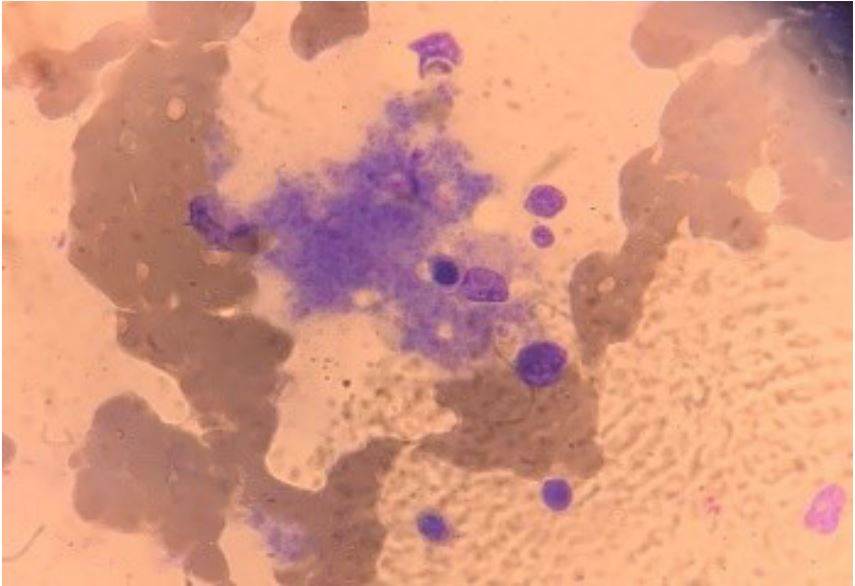

One day after the cyclophosphamide pulse, the pattern of daily fever spells resumed, at short intervals. The patient was initially asymptomatic and much effort was made to identify a possible source of infection. Hemoculture and uroculture were negative and the transthoracic ECG showed normal ventricular function, although a mild to moderate pericardial effusion without vegetations was observed. After two weeks of daily fever, without clinical complaints, and despite treatment with meropenem and vancomycin, the patient’s overall condition worsened, with changes in renal function and need for supplemental nasal oxygen therapy. The bone marrow fluid showed signs of hemophagocytosis, but was negative for parasites and neoplastic cells (Figure 1). A new series of laboratory tests (Table 1, Column 3), along with the findings of hepatosplenomegaly and hemophagocytosis, suggested a diagnosis of MAS. The patient also experienced precordial pain on effort, aggravated by movement, and the ECG displayed diffuse ST segment elevation and PR segment depression in D2 (Figure 2) compatible with pericarditis, despite the use of prednisone 40 mg/day for one month and immunosuppression with cyclophosphamide for 15 days. At this point, another 3-day pulse therapy with methylprednisolone 500 mg was administered. Some clinical improvement was observed, but the fever and tachycardia persisted.

Figure 1: Aspired bone marrow fluid with signs of hemophagocytic activity.